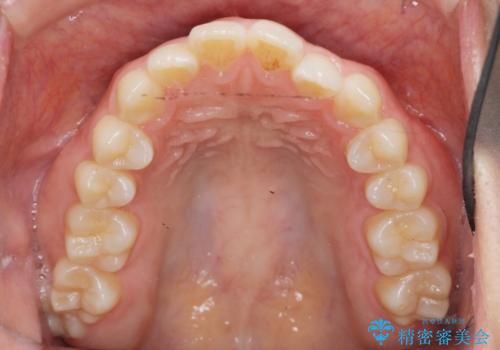

前歯のすれ違い インビザラインで行うマウスピース矯正

- 前歯のガタつき、でこぼこ、前後が逆になっている噛み合わせの改善を求めて来院されました。

治療の装置が目立たず歯ブラシのしやすいマウスピース矯正インビザラインでの治療を計画します。

20時間/日の装用時間をしっかりと守っていただき、きれいな歯並びを手に入れることができました。